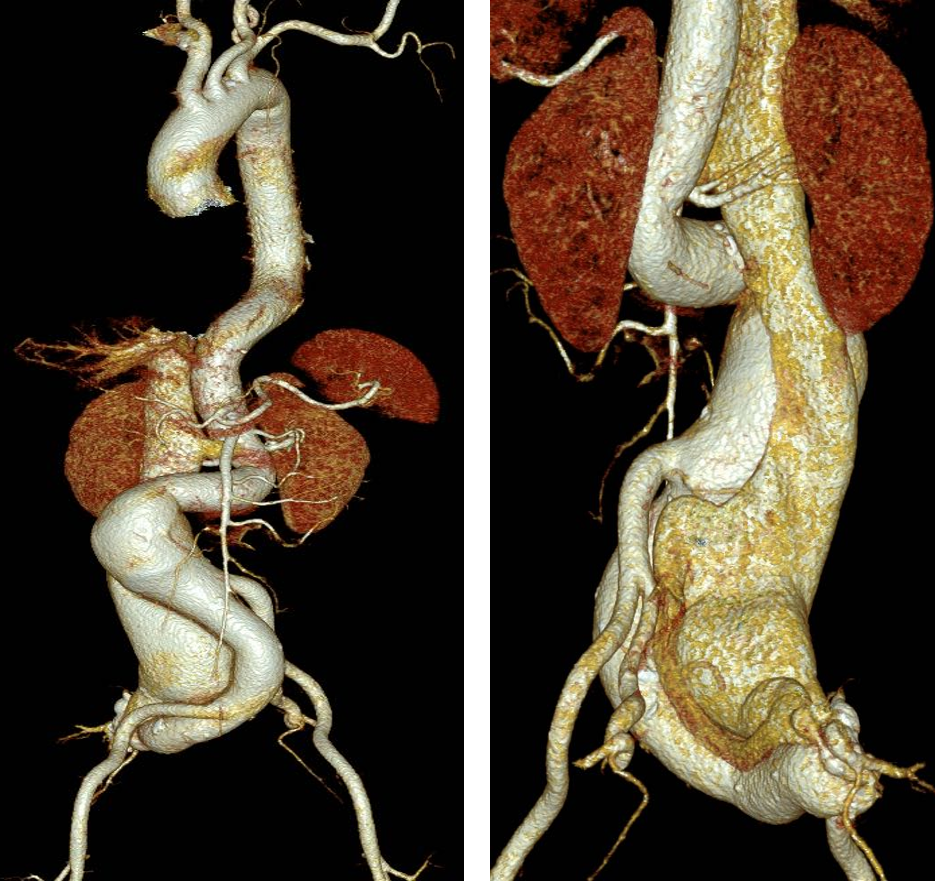

CTA:腹主动脉瘤、右侧髂总动脉及髂内动脉瘤,临近下腔静脉受压、推移且瘤样扩张,右侧髂内动静脉瘘形成

术前CT